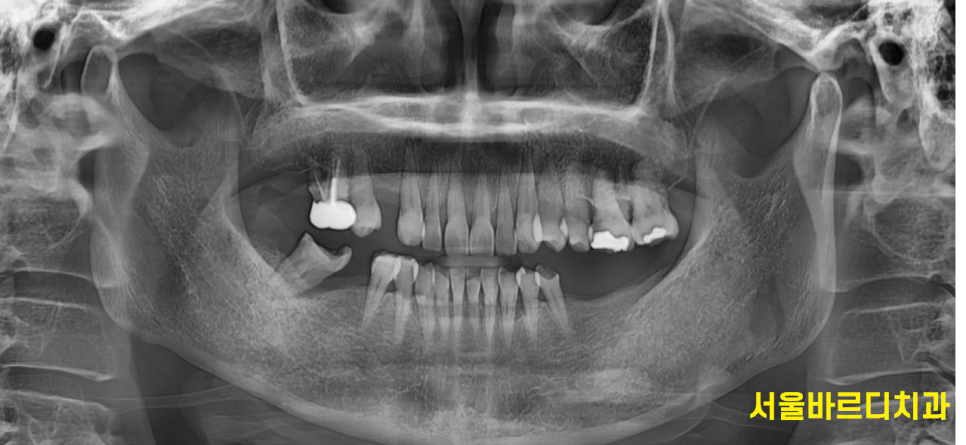

고덕동 치과를 찾아와주신 한 여성 환자분입니다.

코로나때 치료 시기를 놓치고 몇년만에 고덕동 치과를 방문해주셨다 하셨어요

240423

사진만 봐도 오랜만에 오신 것을

확인할 수가 있었습니다.

발치 자국이 안보인다.

-

치아 쓰러짐 관찰